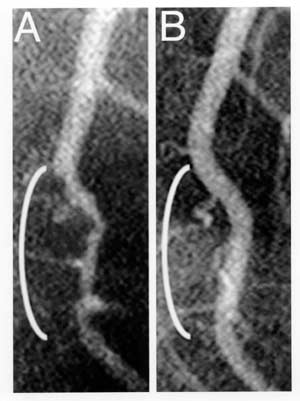

Below are angiograms, imaging of arteries, showing atherosclerosis, arterial blockages, that were reversed by being on plant based diets. The restriction of fat intake was key to reducing the plaque build up.

Coronary angiograms of the distal left anterior descending artery before (A) and after (B) 32 months of a plant-based diet without cholesterol-lowering medication, showing profound improvement.

Caldwell B. Esselstyn, Jr., MD

Cleveland Clinic Foundation